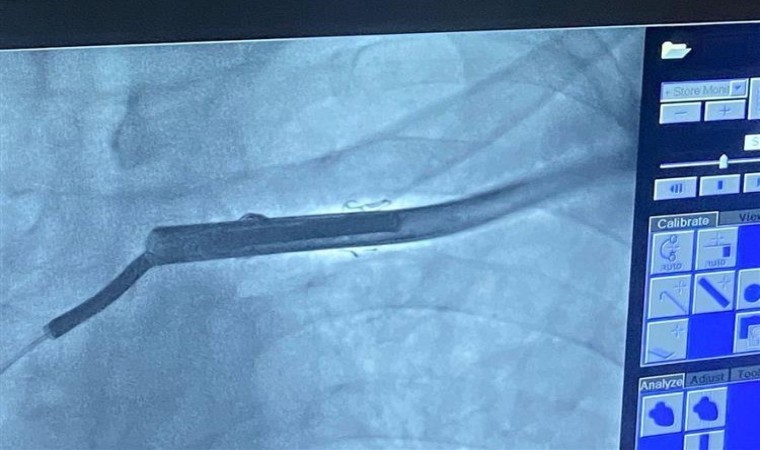

Yaklaşık 5 yıl önce kalp yetmezliği tanısı üzerine kalbindeki ritim bozukluğunu önlemek için şok veren tipte kalıcı kalp pili takılan 56 yaşındaki kadın bir hasta, kalp pilinin şok vermesi üzerine Mardin Eğitim ve Araştırma Hastanesi Kardiyoloji Polikliniğine başvurdu. Yapılan pil kontrolünde verilen şokun uygunsuz olduğu, kablo ölçümlerinde kablonun kırık olduğu tespit edilmesi üzerine kablonun çıkarılması için hastanın yatışı yapıldı. Hastane hekimi ve Artuklu Üniversitesi Tıp Fakültesi Kardiyoloji Ana Bilim Dalı Başkanı Prof. Dr. Mehmet Zülkif Karahan yönetimindeki ekip tarafından yaklaşık 2 saat süren başarılı operasyonla kablo, kalpten çıkarıldı.